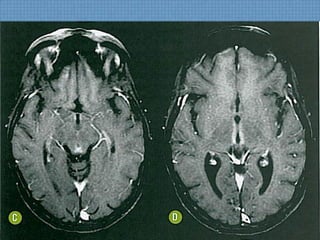

ACHADOS DE IMAGEM

• RM:  Determina diagnóstico e estima prognóstico;

– T1:Hipossinal em topografia subcortical parietoccipal, com

rara impregnação puntiforme pelo Gd;

– T2/FLAIR: Hiperssinal digitiforme parietocciptal, podendo

estender-se para as regiões cerebrais anteriores, além do

NB;

– SWI: Permite diagnóstico de hemorragia de permeio 

Hipossinal;

DIFUSÃO!

Usualmente normal  Só edema vasogênico;

Se restrição  Dano cerebral irreversível;

ACHADOS DE IMAGEM •RM:  Determina diagnóstico e estima prognóstico; – T1:Hipossinal em topografia subcortical parietoccipal, com rara impregnação puntiforme pelo Gd; – T2/FLAIR: Hiperssinal digitiforme parietocciptal, podendo estender-se para as regiões cerebrais anteriores, além do NB; – SWI: Permite diagnóstico de hemorragia de permeio  Hipossinal; DIFUSÃO! Usualmente normal  Só edema vasogênico; Se restrição  Dano cerebral irreversível;